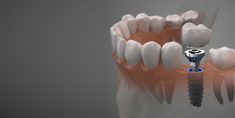

Same Day Dental Implants in Houston TX

If you’re looking to improve your quality of life and replace your missing teeth with the help of dental implants! At VIP Dental Implants, we focus exclusively on using dental implants for replacing your missing teeth. Call us for a free consultation at (832) 224-2615 or visit us at VIP Dental Implants in Houston, TX.